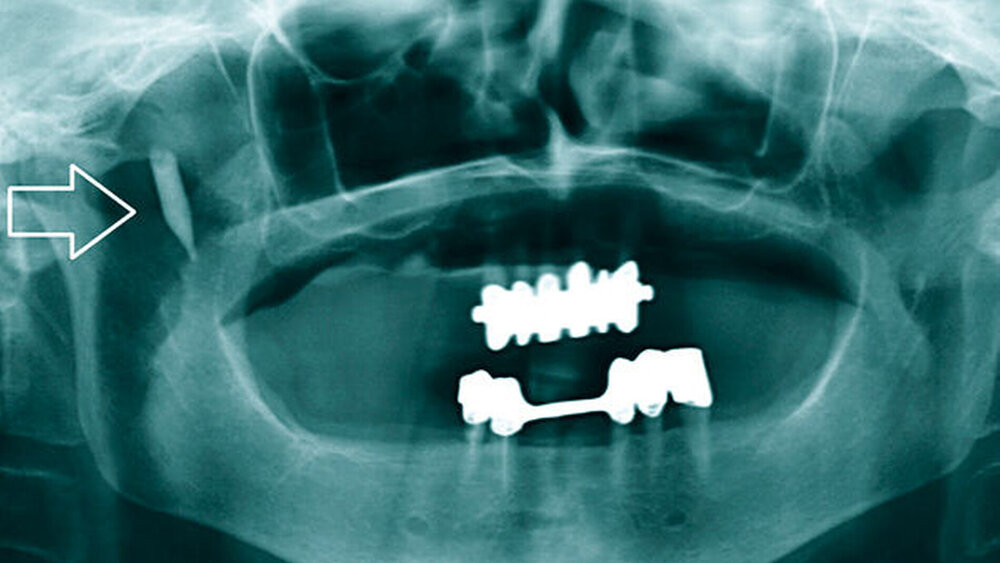

In unserer Praxis wurde zunächst ein Orthopantomogramm (OPG) angefertigt, auf dem neben einem prothetisch und konservierend versorgten Restgebiss im Bereich des rechten Kiefergelenks eine unklare, länglich-ovale Verschattung erkennbar war (Abbildung 1). Differenzialdiagnostisch vermuteten wir einen Fremdkörper oder eine langstreckige Gefäßverkalkung. Die Patientin konnte sich aber an keine Verletzung oder mögliche andere Ursachen einer Fremdkörpereinsprengung erinnern, woraufhin eine Computertomografie (CT) zur weiteren Diagnostik veranlasst wurde.